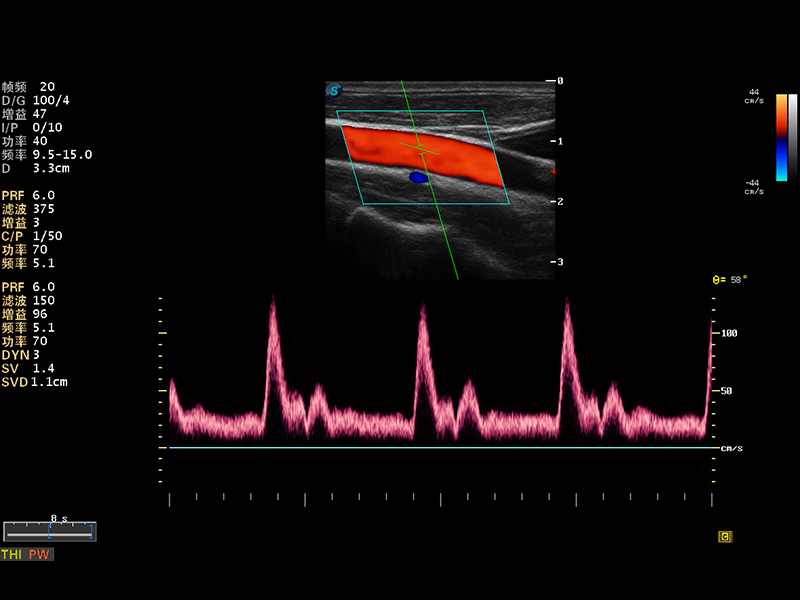

S8 EXP便携式彩色多普勒超声诊断仪是球速体育入口研发的高端全身应用型便携彩超。高通道的VIS平台融合可视化(Visual)、智能化(Intelligent)和人性化(Smart)的特点,配以球速体育入口自主研发生产的探头大家族,使您能够快速、准确的获得病人信息,提高工作效率的同时减轻疲劳。

成像技术

多波束形成器

μ-Scan微米成像

谐波成像

实时宽景成像

空间复合成像